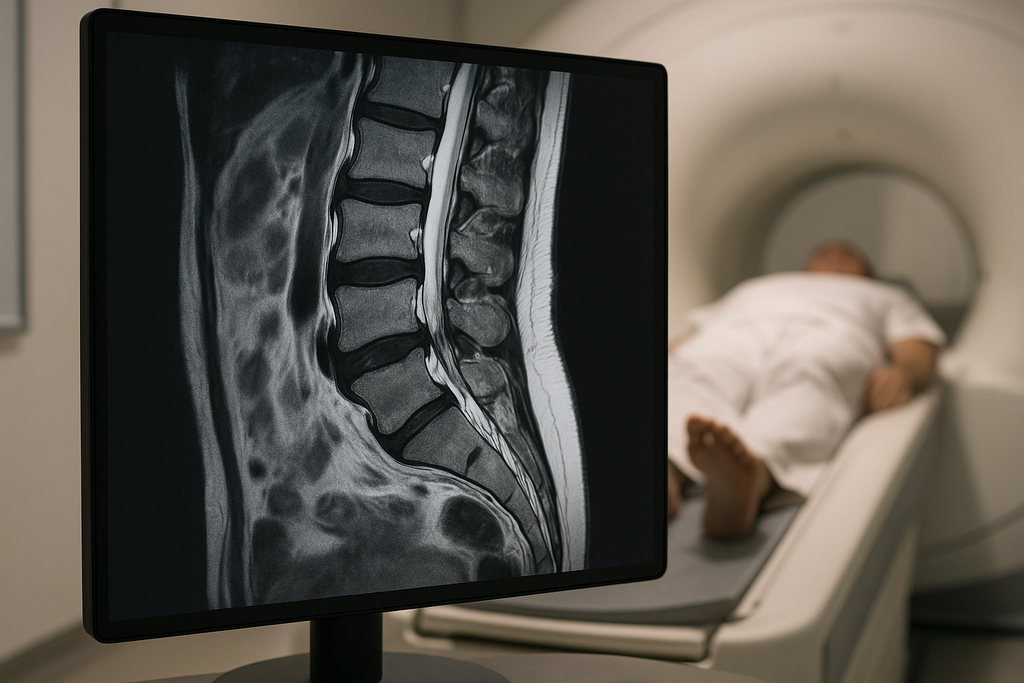

MRIやレントゲンで分かるのは「構造」だけ

MRIやレントゲンはとても優れた検査です。

例えば次のような異常は画像で確認できます。

椎間板ヘルニア

脊柱管狭窄症

骨折

腫瘍

強い炎症

つまり、骨や椎間板などの構造の問題を調べる検査です。

しかし、このような組織の変化は

MRIやレントゲンではほとんど分かりません。